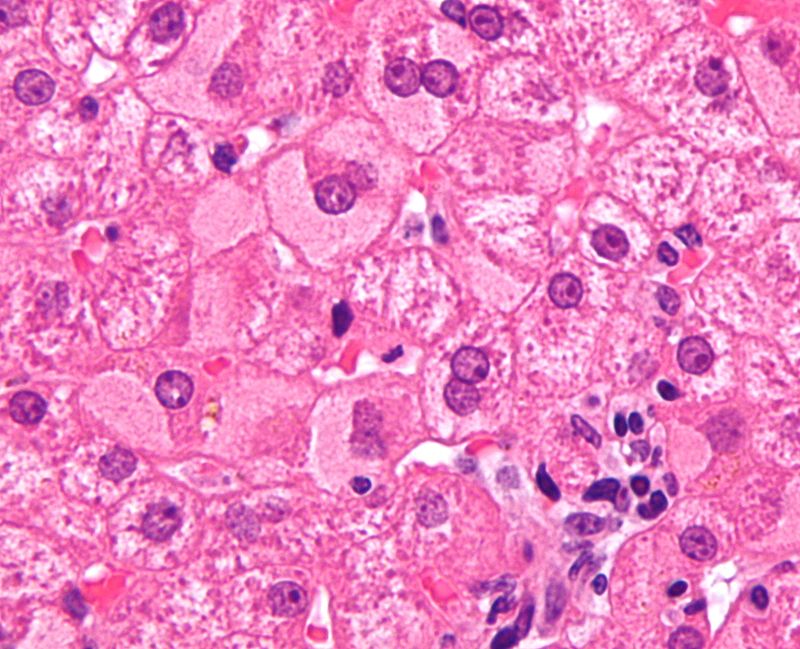

Hepatocyte apoptosis is a sign of inflammation, which affects the lobules of the liver and the portal tracts.

Hepatocyte swelling and the development of Mallory bodies are it’s defining features.